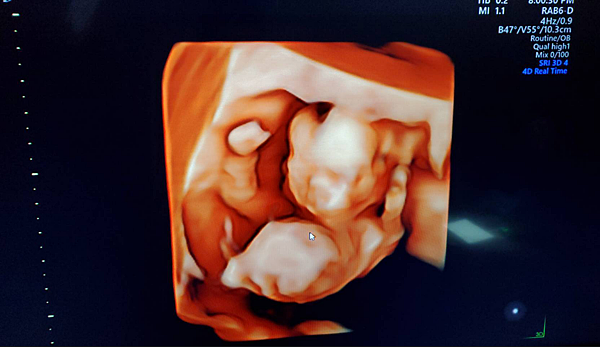

每次在這邊照超音波的時候 都有立體的4D超音波影像可以看

不在只是黑白的影像 可以看到他手腳摸來摸去的樣子

輪廓也更加的逼真 稍微可以看得出一點是爸爸還媽媽的樣子

這次二寶每次拍照都在摸頭摸臉擺pose~張主播看到都要融化了哈哈哈